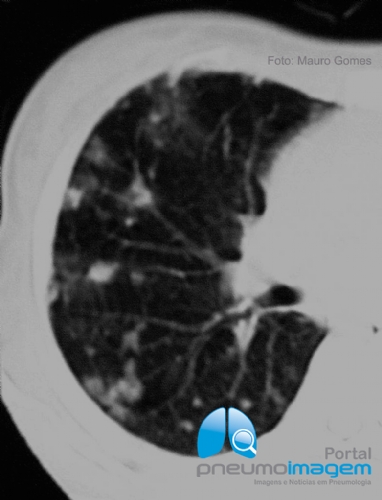

CASO CLÍNICO #50

Você conhece o nome desse sinal e o que ele significa? Deixe seus comentários abaixo!

Do you know this sign and what it means? Write your comment below!